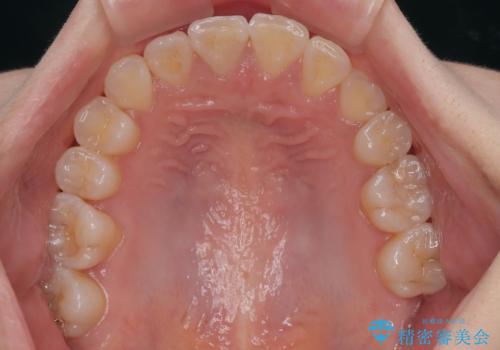

- 左上の前歯のがたつきを主訴に来院された患者様です。

上顎歯列が下顎の歯列に対して狭小であり、一部下顎の奥歯が上顎よりも外側に位置している状態でした。

上顎の歯列を拡大しスペースを設け、さらに左上の小臼歯を一本抜歯し左上の八重歯を歯列内に入れ整えていくことにしました。